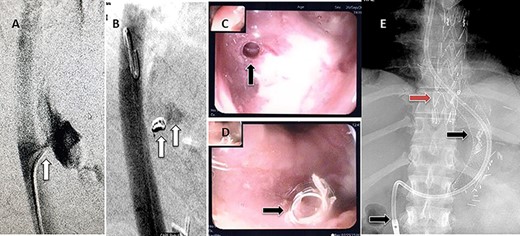

(A) Aortography showed active contrast extravasation to the esophagus trough the fistula. (B) Coli embolization of the AEF with contrast beyond the coil. (C) Esophagogastroduodenoscopy revealed the site of the fistula and the coil embolization in the stomach. (D) An esophageal stent was placed extending to the stomach and the aortic stent in place. Feeding tube in place.

Esophagogastroduodenoscopy revealed thoracic endovascular aortic stent can be seen in the distal esophagus. (B) PET scan showing increase FDG activity around the distal aortic stent.